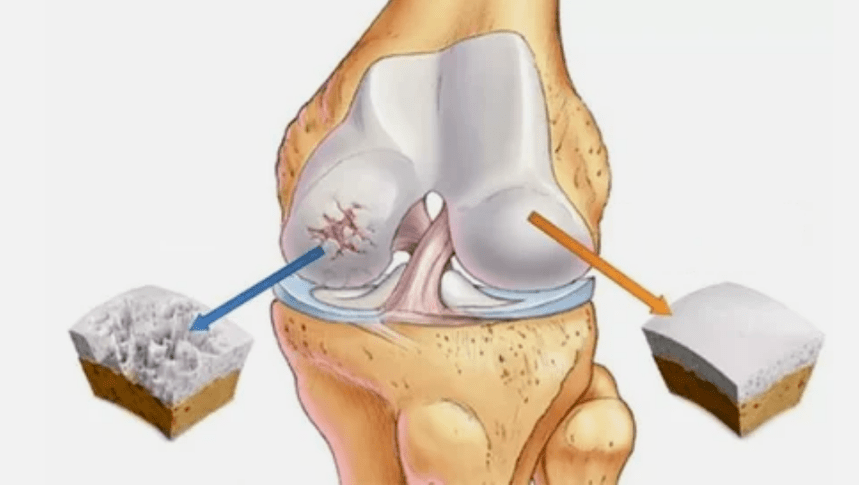

- Die primäre Läsion beeinflusst den hyalinen Knorpel. Bei Kreislaufstörungen tritt die Verschlechterung der pathologischen Kraft auf. Es ist der erste Schritt oder die erste Ursache, die eine Arthrose auftreten kann.

- Hyalin -Beschichtungspathologien. Das Abnehmen des Knorpels führt zum Ersatz seiner pathologischen Gewebe: Knochenstrukturen.

- Anomale Wachstum erscheinen im Knorpel - Osteophyten.

- Die Verletzung der natürlichen Anatomie des Knorpels und der Knochen verursacht die Überlastung gesunder Knorpelbereiche. Die Zerstörung von gemeinsamen Stoffen ohne Behandlung verläuft ständig und führt zu Behinderungen.

- Reduzierung der Lücke in der gemeinsamen Lücke, die im Bild bemerkenswert wird. Das Vergewaltigungsstadium wird vom Diagnose-Tantnologen bestimmt. Der Patient spürt die Komplexität oder Unfähigkeit, das Glied vollständig zu begradigen und zu falten.

Um eine Diagnose zu stellen, untersuchen Rheumatologen die Beschwerden des Patienten und verschreiben eine X -Ray -Untersuchung. Meistens wird die Radiographie in 2 Projektionen verwendet. Der Arzt analysiert das Vorhandensein von Verteilungsstörungen in den Hyalinenknorpel- und Knochenverbindungen. Wenn die Gelenkspalte verringert wird, die Knochen verzögert oder abgeflacht sind, gibt es zystische Formationen auf der Knorpeloberfläche, Osteophyten sind offensichtliche Anzeichen einer Arthrose. Während der Inspektion zeigt die Arthrose auf die Instabilität der Artikulation an: die Achse der Gliedmaßen und die Subluxation wird verändert.